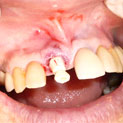

Es una técnica, pero sobre todo es una filosofía de trabajo. Ha sido descrita y registrada por nosotros y esta basada en un hecho sencillo, pierdes un diente o extraemos el diente enfermo y problemático, y en la misma sesión, el mismo día colocamos el diente nuevo con una mejora de la estética evidente.

En estos casos han sido tratados con la filosofía de all-at-once, en la

misma sesión: